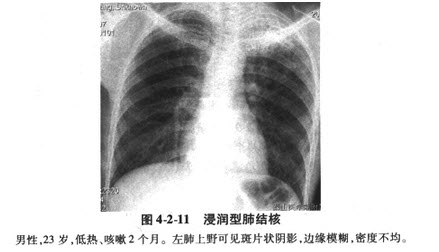

浸润型肺结核

肺渗出(浸润)性病变:浸润型肺结核.